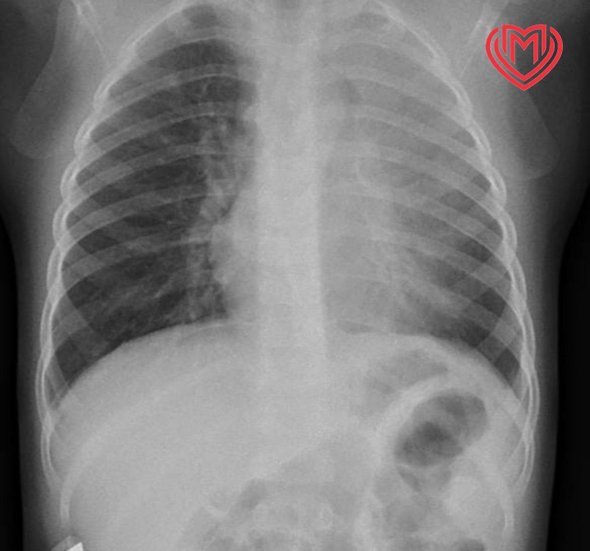

На четвертый день улучшений не наступило и ребенку вызвали скорую, которая доставила пациента в больницу имени Башляевой. Там врачи сделали рентген грудной клетки, которая показала левостороннюю пневмонию. Пациента госпитализировали в стационар. С учетом анамнеза и других данных врачи клиники заподозрили инородное тело в дыхательных путях, которое могло стать причиной пневмонии. После предоперационной подготовки мальчику провели эндоскопию.

По данным видеобронхоскопии в дистальном отделе левого главного бронха обнаружили инородное тело продолговатой формы размером 4×1 см, которое оказалось куском мяса. Его извлекли при помощи аспирационной тяги, бронхи обработали, и ребенок смог свободно дышать.

фото: t.me/bashlyaevoydgkbdzm